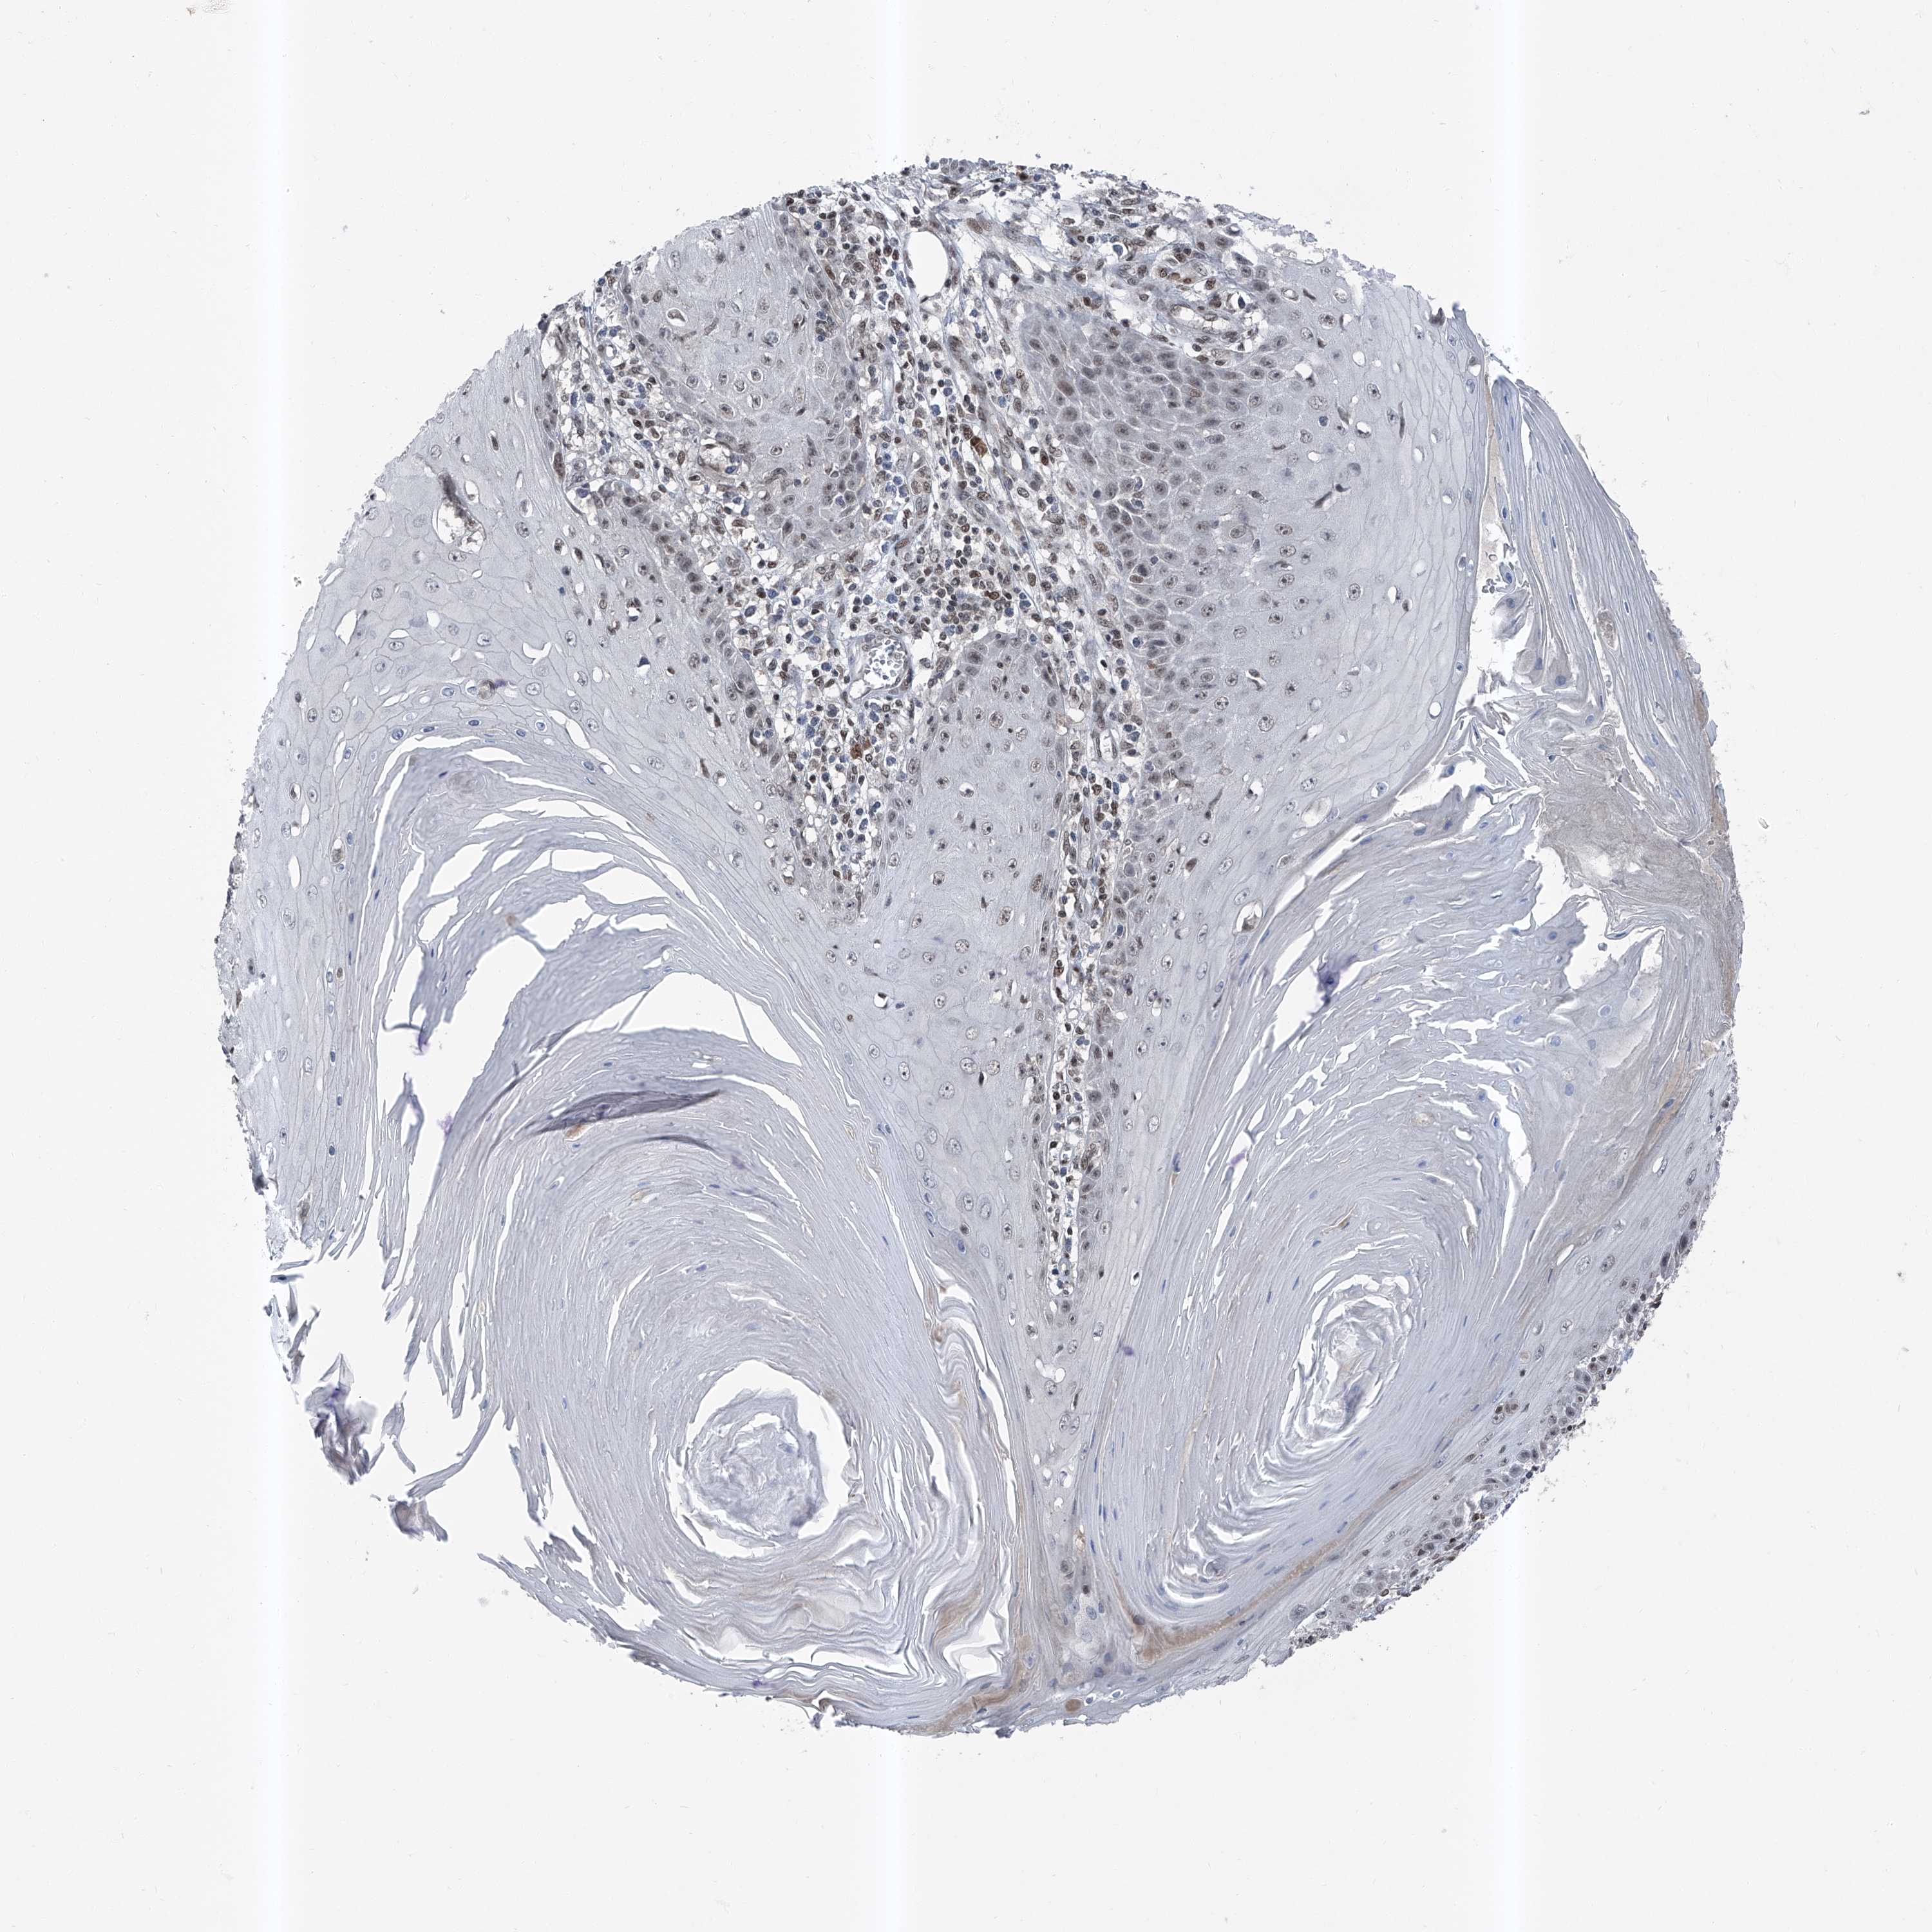

Basal cell and squamous cell cancer

SKIN CANCER - Protein expressioni

A mouse-over function shows sample information and annotation data. Click on an image to view it in a full screen mode. Samples can be filtered based on level of antibody staining by selecting one or several of the following categories: high, medium, low and not detected. The assay and annotation is described here.

Each image is clickable and will lead to virtual microscopy that enables deeper exploration of all samples and also displays staining intensity scores, fraction scores and subcellular localization as well as patient and tissue information for each sample.

Antibody HPA030472

Antibody HPA036584

Basal cell carcinoma

Squamous cell carcinoma, NOS

Squamous cell carcinoma, metastatic, NOS